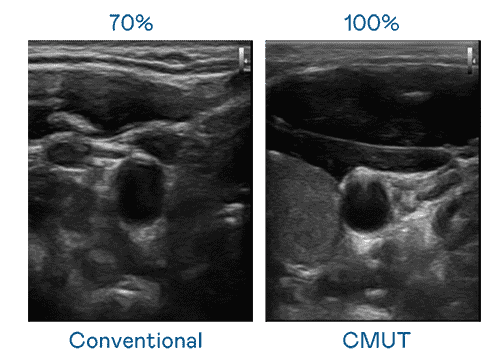

CMUT 技术是一种用电容式微机电元件来产生超音波讯号的技术。。与传统 PZT 压电式技术相比,,,CMUT 频宽增加 30%,,,,更宽频的超音波讯号让影像解析度大幅提升,,是实现高影像品质医疗超音波扫描、、、促进精准医疗发展的关键技术。。。

大频宽带来超清晰影像

超音波影像的解析度高低,,首先取决于探头能发出的讯号频宽。。。尊时凯龙 CMUT 可提供高清晰的超音波讯号,,,,提供高频宽、、高灵敏度、、、影像纹理细节更高的超音波影像,,协助医护人员缩短影像判读时间及利用精准的医疗影像进行诊断。。。。